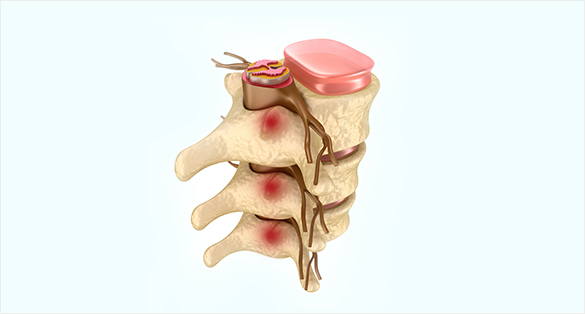

추간관절치료

디스크는 척추 관절에도 염증이 생깁니다.

척추관절 사이에 약물치료를 하는 시술입니다.